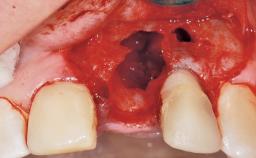

Immediate Flapless Placement of an Implant in a Maxillary Left Central Incisor Site

A 42-year-old female patient was referred to our clinic at the School of Dentistry of the University of São Paulo in November 2004, presenting a deficient restoration in the upper left central incisor. The clinical examination revealed no gingival retraction or any signs of gingival inflammation and, therefore, previous periodontal treatment was not considered. The patient presented a high lip line at full smile and a thin tissue biotype. This combination characterized a high-risk situation from an anatomic point of view, which required careful preoperative planning and cautious surgical execution.

Placement Protocol Immediate implant placement

Tooth Site Maxillary incisor or canine

Socket Morphology Single-root socket

Socket Integrity Sufficient, with intact bone walls

Bone Volume Sufficient, with intact walls